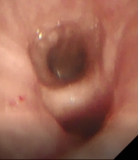

术前支气管 术中改变 术后支气管

接受新疗法的患者两年前就明确诊断为慢阻肺,之后长期吸入大剂量信必可治疗,但咳痰和气急的症状仍控制不佳,本次入院复查发现肺功能明显下降,为中度阻塞性通气功能障碍。4月15日,王昌惠主任、李萍主任医师和李譞主治医师运用冷冻喷雾技术,成功完成COPD患者的支气管粘膜消融手术,术后患者无不良反应发生,第二天即顺利出院。症状得到明显改善,患者对王昌惠教授团队的感激之情溢于言表。

基于以上发现,此次在上海申康医院发展中心重大临床研究项目支持下,团队进一步研究发现通过冷冻治疗设备控制,冷冻时设备将液氮输送至导管冷冻端,使冷冻端表面温度骤降,吸收环境温度,组织结冰,杀死病变组织细胞。解冻时,设备将常温氮气输送至导管冷冻端,使组织温度升高,进一步破坏病变组织细胞,达到治疗目的。